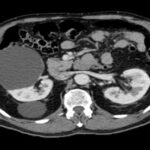

La Categoría I define la lesión como densidad agua (0-20 UH), sin septos o calcificaciones, ausencia de polos sólidos y sin realce a la administración de medio de contraste yodado IV.(19, 20) Su clasificación sería de quiste simple benigno y no requeriría ningún tipo de evaluación posterior. Son lesiones asintomáticas que rara vez requieren tratamiento. No es necesario realizar controles posteriores (Anexos 3 y 4).

La Categoría II define una lesión con septos finos lisos (< 1mm), calcificaciones lineales continuas o discontinuas o lesiones densas homogéneas en la pared o tabique pero que no experimentan realce a la administración de medios de contraste yodado IV en TC o paramagnéticos en RMI. Su clasificación es de lesión benigna (proteáceos, hemorrágicos, infecciosos).(19, 20) Estos quistes son hiperdensos (40-90 UH < 3cm), mínimamente complicados y no precisan cirugía, deben ser controlados (Anexos 5 y 6).

- Bosniak I: el 80% de los quistes (418 pacientes) fueron clasificados como Bosniak I, es decir, quistes simples hallados incidentalmente en tomografía computada (TC) y sin necesidad de seguimiento adicional. De estos, 268 pacientes eran de sexo masculino y 150 de sexo femenino (Anexos 17 y 18).

- Bosniak II: el 10% de los quistes (55 pacientes) fueron catalogados como Bosniak II, correspondientes a quistes benignos. Esta categoría incluyó a 36 pacientes de sexo masculino y 19 de sexo femenino (Anexos 19 y 20).